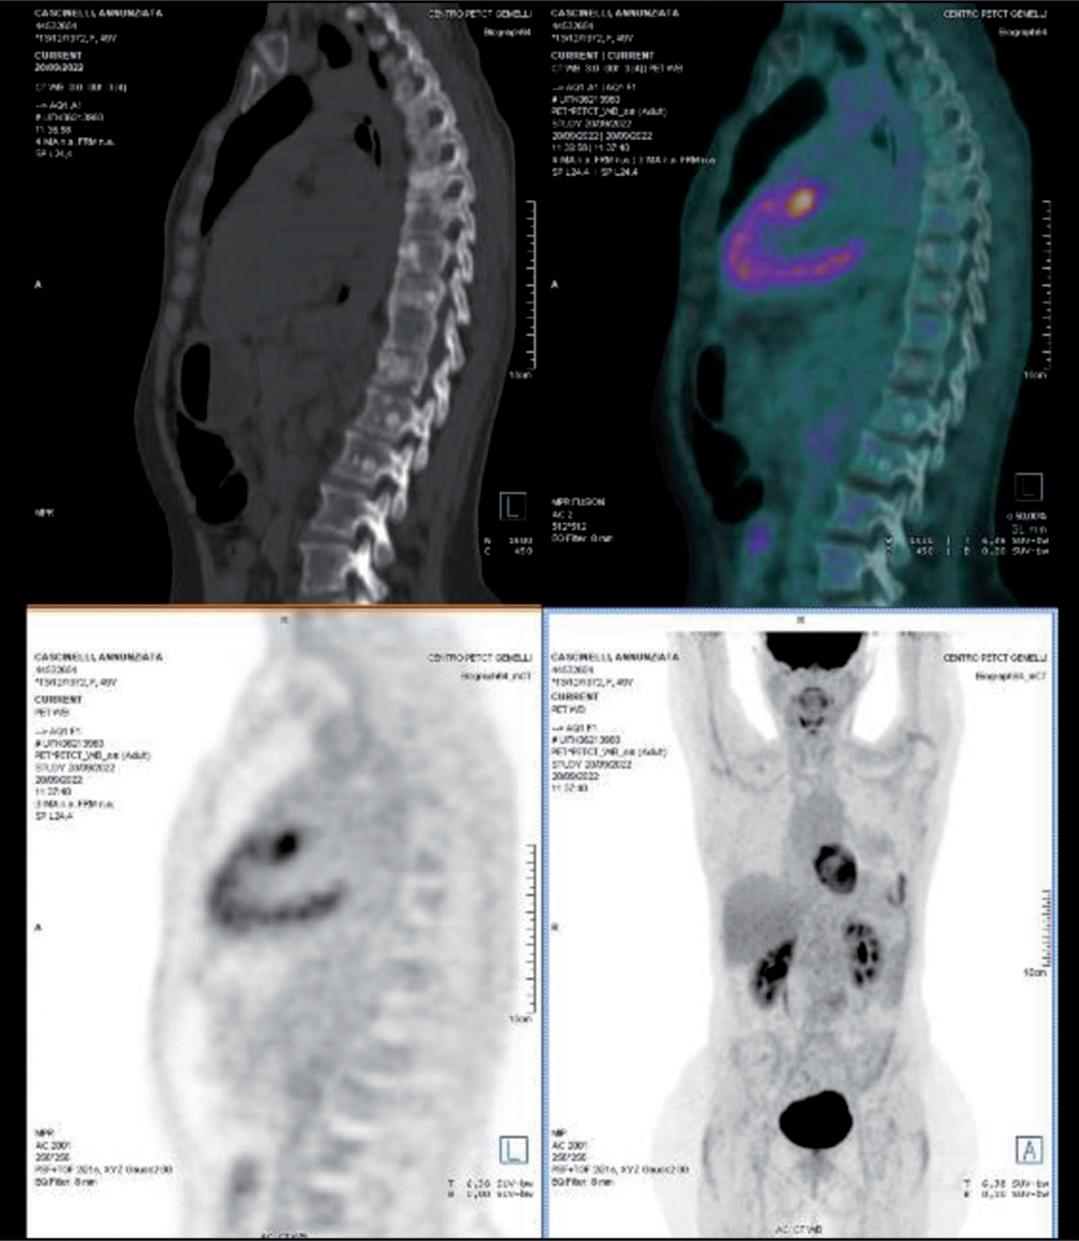

A giugno 2017 comparsa di metastasi ossea sternale e polmonari bilaterale alla PET/TC eseguita per persistenza di algie sternali.

trastuzumab 6 mg/kg (loading dose 8 mg/kg d1c1) e docetaxel 75 mg/mq q21 x 6 cicli ottenendo risposta metabolica parziale alla PET/TC di rivalutazione.

Prosegue con la terapia di mantenimento con pertuzumab, trastuzumab e letrozolo fino a ottobre 2022, quando viene interrotta per progressione linfonodale e polmonare di malattia alla PET/TC di rivalutazione (figura 2).

Da dicembre 2022, considerando i dati dello studio DESTINY-Breast034,5, viene avviata terapia con T-DXd 5,4 mg/kg q21 ottenendo risposta metabolica completa alla rivalutazione PET/TC di marzo 2023 (figura 3). Ad aprile 2024 terapia ancora in corso (16 somministrazioni ricevute).

Figura 2. PET/TC con FDG alla progressione di malattia prima dell’avvio di T-DXd.

Figura 3. Prima rivalutazione PET/TC con FDG in corso di T-DXd.